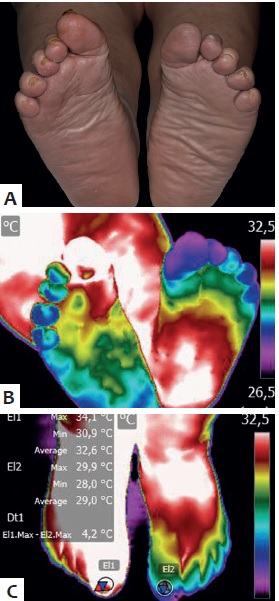

Como a Neuropatia Diabética Afeta a Sensibilidade Térmica

A verdade é a seguinte: a neuropatia causa diminuição da percepção de calor, dor e tato nos pés. Isso significa que a perda de sensibilidade impede a detecção de água excessivamente quente. Você pode estar com os pés numa água escaldante e não sentir o perigo, o que é um risco enorme para a sua saúde dos pés diabéticos.

Cuidados com o Pé Diabético: Inspeção Diária e Prevenção de Úlceras

Além da temperatura da água, a inspeção diária dos pés é fundamental. Verifique se há cortes, bolhas, vermelhidão ou inchaço. Qualquer feridinha, por menor que seja, precisa de atenção. A prevenção de úlcera diabética é um trabalho contínuo e minucioso.

Diariamente, sem exceção. A inspeção é tão crucial quanto testar a temperatura da água.

Faça isso após o banho, com os pés bem secos. Use um espelho para ver as solas. Procure por qualquer alteração: vermelhidão, rachaduras, bolhas ou cortes. Encontrar algo no início muda completamente o prognóstico.